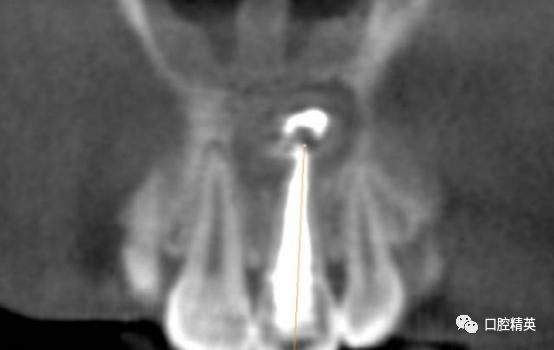

CBCT检查发现21内吸收,已做根充。根尖周可见约10mm*7mm*7mm范围低密度影像,近11,22根尖区。边界清楚。可见超充药物,查看病历曾使用碘仿和VITAPEX。